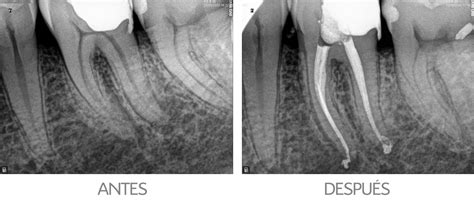

- Radiografía diagnóstica: Permite ver cómo son los conductos (forma, longitud, calcificaciones, y más).

- Apertura de la cámara pulpar: Para tener acceso a los conductos.

- Instrumentación y limpieza: Con ayuda de la instrumentación adecuada se limpian los conductos radiculares y se procede a la obturación y sellado de los mismos.